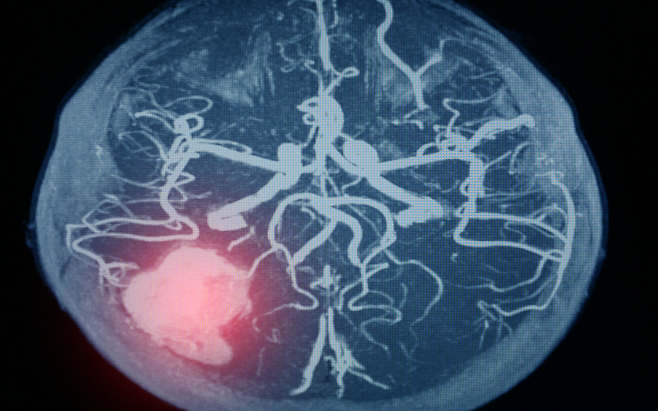

뇌출혈은 예고 없이 찾아오고, 한 번 겪으면 삶 전체를 송두리째 흔든다. 단 한 번의 출혈로 말이 어눌해지거나, 반신마비가 오기도 하고, 심할 경우 목숨까지 잃을 수 있다.

뇌출혈의 가장 큰 원인은 고혈압이다. 높은 혈압은 뇌혈관을 약하게 만들고, 결국 작은 충격에도 혈관이 터지게 한다. 혈압은 숫자가 아니라 생명줄이다. 하루 10분 걷기, 싱겁게 먹기, 충분한 수면, 스트레스 관리.